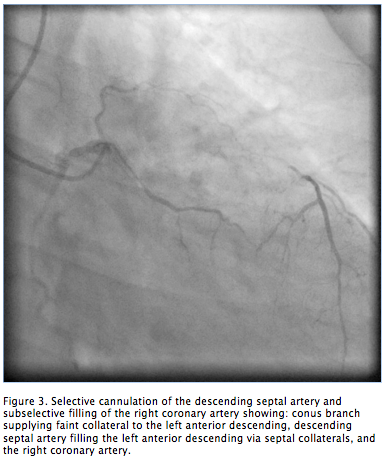

Figure 3. Selective cannulation of the descending septal artery and subselective filling of the right coronary artery showing: conus branch supplying faint collateral to the left anterior descending, descending septal artery filling the left anterior descending via septal collaterals, and the right coronary artery (click thumbnail to view larger image).

There were two collateral systems supplying the LAD. These were: (1) the DSA originating from the right coronary cusp giving collaterals to the septal branch and filling the LAD to the apex (Figures 2 and 3); and (2) collaterals from the conus branch of the RCA reaching the first septal branch of the LAD (Figures 3 and 4). Both collateral systems were small in size. The dominant RCA had a focal segment of 60%-70% stenosis (Figure 4). Left ventricular systolic function was normal. The left circumflex (LCX) had mild disease. The patient underwent successful bypass surgery with grafts to the LAD as well as RCA and had uneventful recovery.

In a postmortem angiographic study, Rodriguez et al3 described an accessory artery that helped supply the cardiac interventricular septum in 12% of human hearts and up to 66% of the hearts in other animal species. The described artery originates close to the right coronary orifice, descends through the superior septal border, and ramifies in the interventricular septum. The vessel was referred to as the “descending septal artery.” The DSA was described as arising from the first centimeter of the RCA, from a common orifice with the RCA, a common orifice with the conus branch, or from an independent ostium in the right coronary cusp. The DSA was two times more likely to be present if there was coronary artery occlusion. The authors concluded that this branch is more likely to be a potential source of collateral circulation, and the artery has not gained the attention it deserves. Our patient had severe occlusive coronary artery disease with preserved left ventricular function. Another postmortem stereoscopic radiography study4 performed to understand the blood supply of the conduction system described the descending septal branch as supplying the proximal conduction system in 68% of human hearts studied. The author studied 112 human hearts and half of the patients with the descending septal branch had severe coronary disease. The descending septal branches arose directly from the RCA, from the first conal branch of the RCA, or from a separate aortic ostium in 58%, 25%, and 16.7% of the patients, respectively. Anastomosis was observed between the DSA and septal branches of the LAD artery in hearts with severe coronary artery disease. Our patient’s angiography revealed a significant collateral circulation to an occluded LAD from the DSA (Figures 2 and 3). Failure to identify the target on the LAD might have compromised the treatment of our patient.